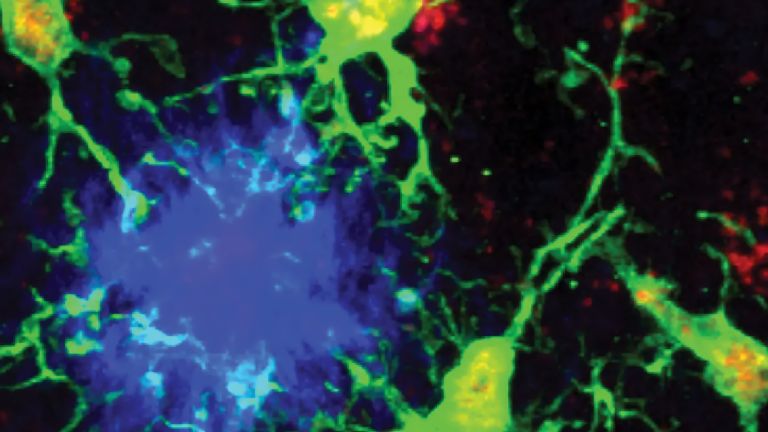

Ein Blutgefäß im Gehirn ist verstopft oder geplatzt, es fehlt an Nährstoffen und Energie, die Zellen sterben ab. Das klingt verständlich und einfach, ist es aber nicht. Durch den versiegenden Blutfluss werden ganze Kaskaden von Ereignissen ausgelöst, die seit Jahrzehnten Heerscharen von Forschern beschäftigen, und die doch noch längst nicht im Detail verstanden sind. Das gilt auch für die Rolle der kleinsten Zellen des Nervensystems, den Mikroglia. Im gesunden Gehirn passen sie auf, dass nichts das Gehirngewebe schädigt. Nach dem Schlaganfall schwingen sie selber das Schwert. Und hören einfach nicht auf damit.

Dabei ist die Feuerwehr, sprich: die Mikroglia, nie inaktiv. Sie liegen in regelmäßigen Abständen verteilt zwischen anderen Zellen, strecken ihre Ausläufer aus und interpretieren darüber die Umgebungssignale. Diese kann man laut Kettenmann in zwei Kategorien einteilen: On- und Off-Signale: "On-Signale sind solche, die neu hinzukommen. Zum Beispiel Lipopolysaccharid." Dieses Molekül aus Bakterienmembranen ist wie ein Erkennungszeichen für Eindringlinge, die im Nervensystem nichts zu suchen haben. Kommen Mikroglia mit ihm in Kontakt, werden sie größer, nehmen eine amöboide Form an, und wandern zur Aktivierungsstelle. Und wenn es sich dabei um ein Bakterium handelt, nehmen sie es in sich auf und verdauen es. Nach getaner Arbeit wird die Zelle wieder inaktiviert.

Mikroglia

Mikroglia/-/microglia

Der kleinste Typ der Gliazellen ist Teil des zellulären Immunsystems und unter anderem zuständig für die Entfernung abgestorbener Neurone. Mikroglia können sich amöbenartig fortbewegen.